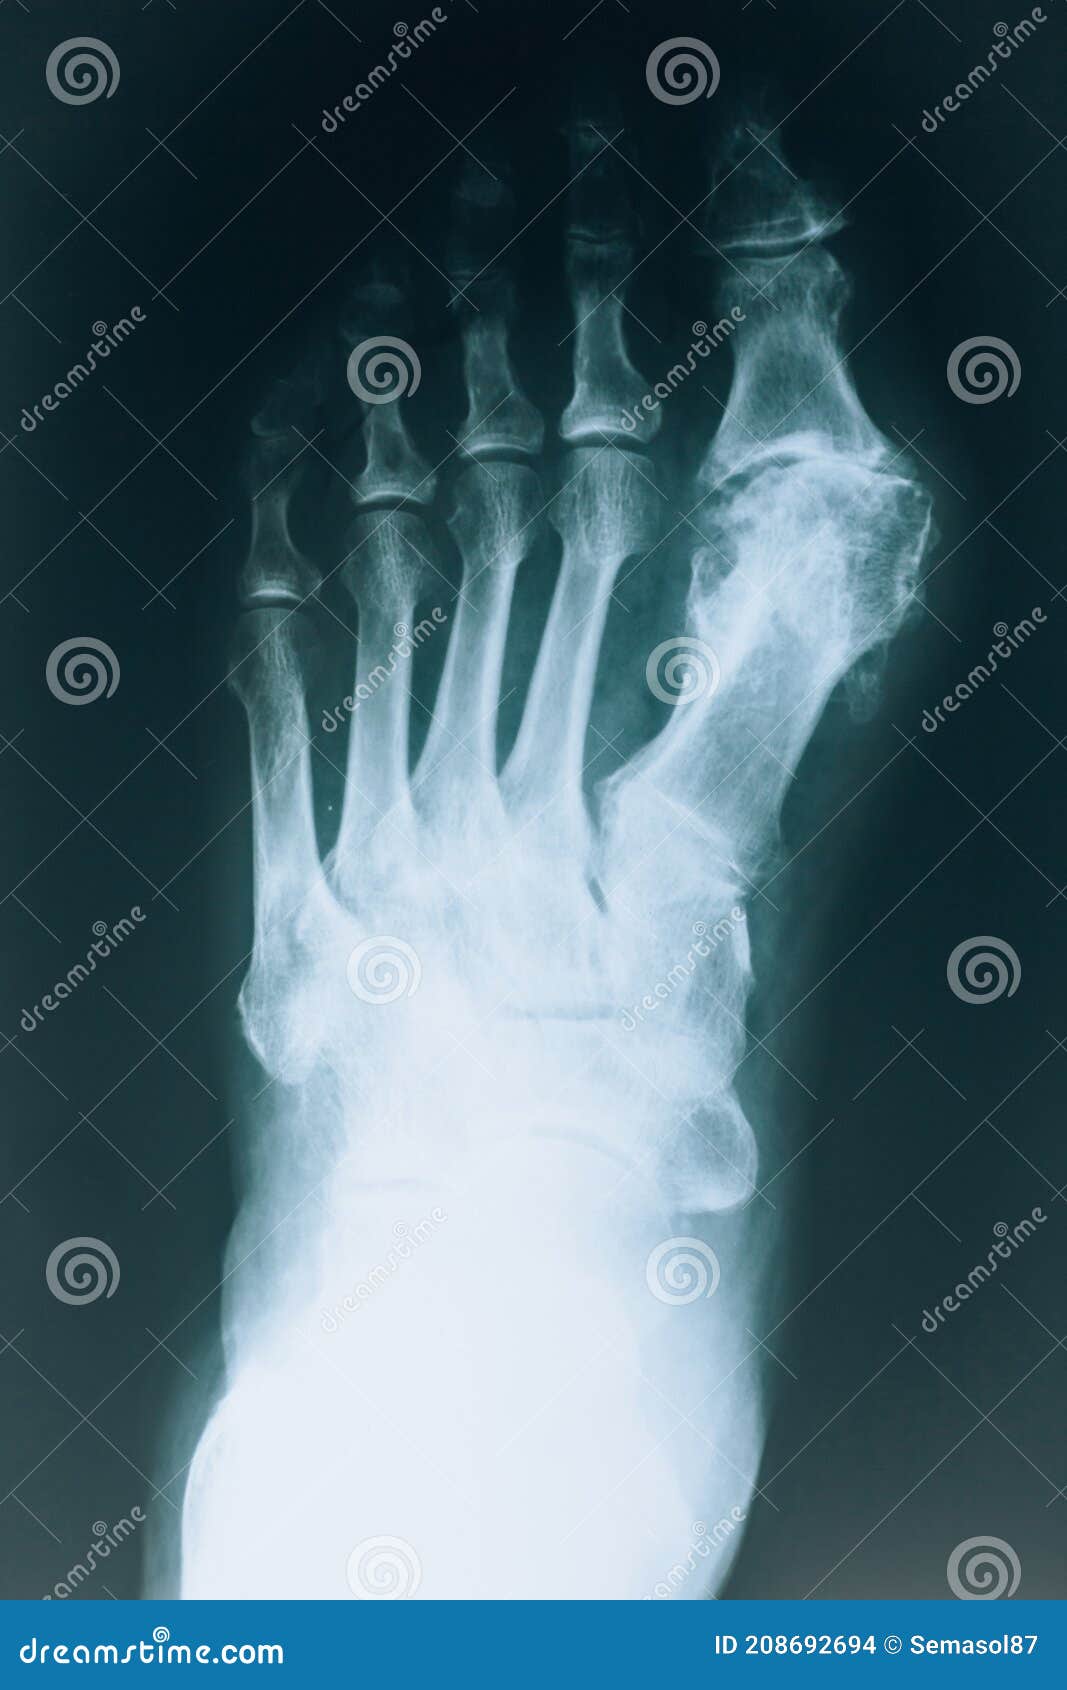

Xray of the Foot Skeleton. Human Leg Bones Stock Illustration Foot Bones X Ray The image displays the soft tissues and bones of your foot. The series is often utilized in emergency departments after trauma or. Find out the clinical significance,. Learn about the 26 bones, joints, and muscles of the foot and how they are visualized on foot radiographs. Accessory ossicles of the feet are common developmental variants with almost 40 having been. Foot Bones X Ray.